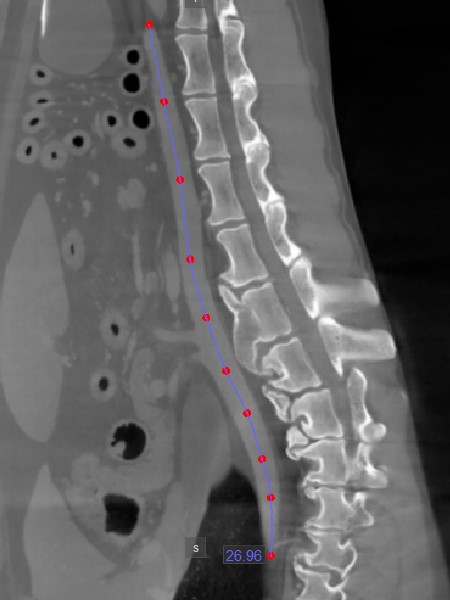

Pfadlänge¶

Das Werkzeug Pfadlänge

ermöglicht es Benutzern, die Länge unregelmäßiger Linien oder die Kontur komplexer Formen entlang eines nichtlinearen Pfads zu messen.

Wählen Sie das Werkzeug Pfadlänge

aus und weisen Sie es einer der verfügbaren Maustasten zu. Starten Sie die Messung, indem Sie Punkte entlang eines nichtlinearen Pfads auf der aktiven Bildschicht setzen. Während der Benutzer die Punkte setzt, verbindet die Software sie automatisch und erstellt den Pfad.

Schließen Sie die Messung ab, indem Sie beim Setzen des letzten Punkts des Pfads doppelklicken oder die rechte Maustaste verwenden, um den Pfad sofort zu berechnen. Die Länge des Pfads wird zusammen mit der Messung angezeigt.

Ändern Sie den Pfad, indem Sie einen der Punkte, die ihn beschreiben, mit dem Werkzeug Standard

verschieben.